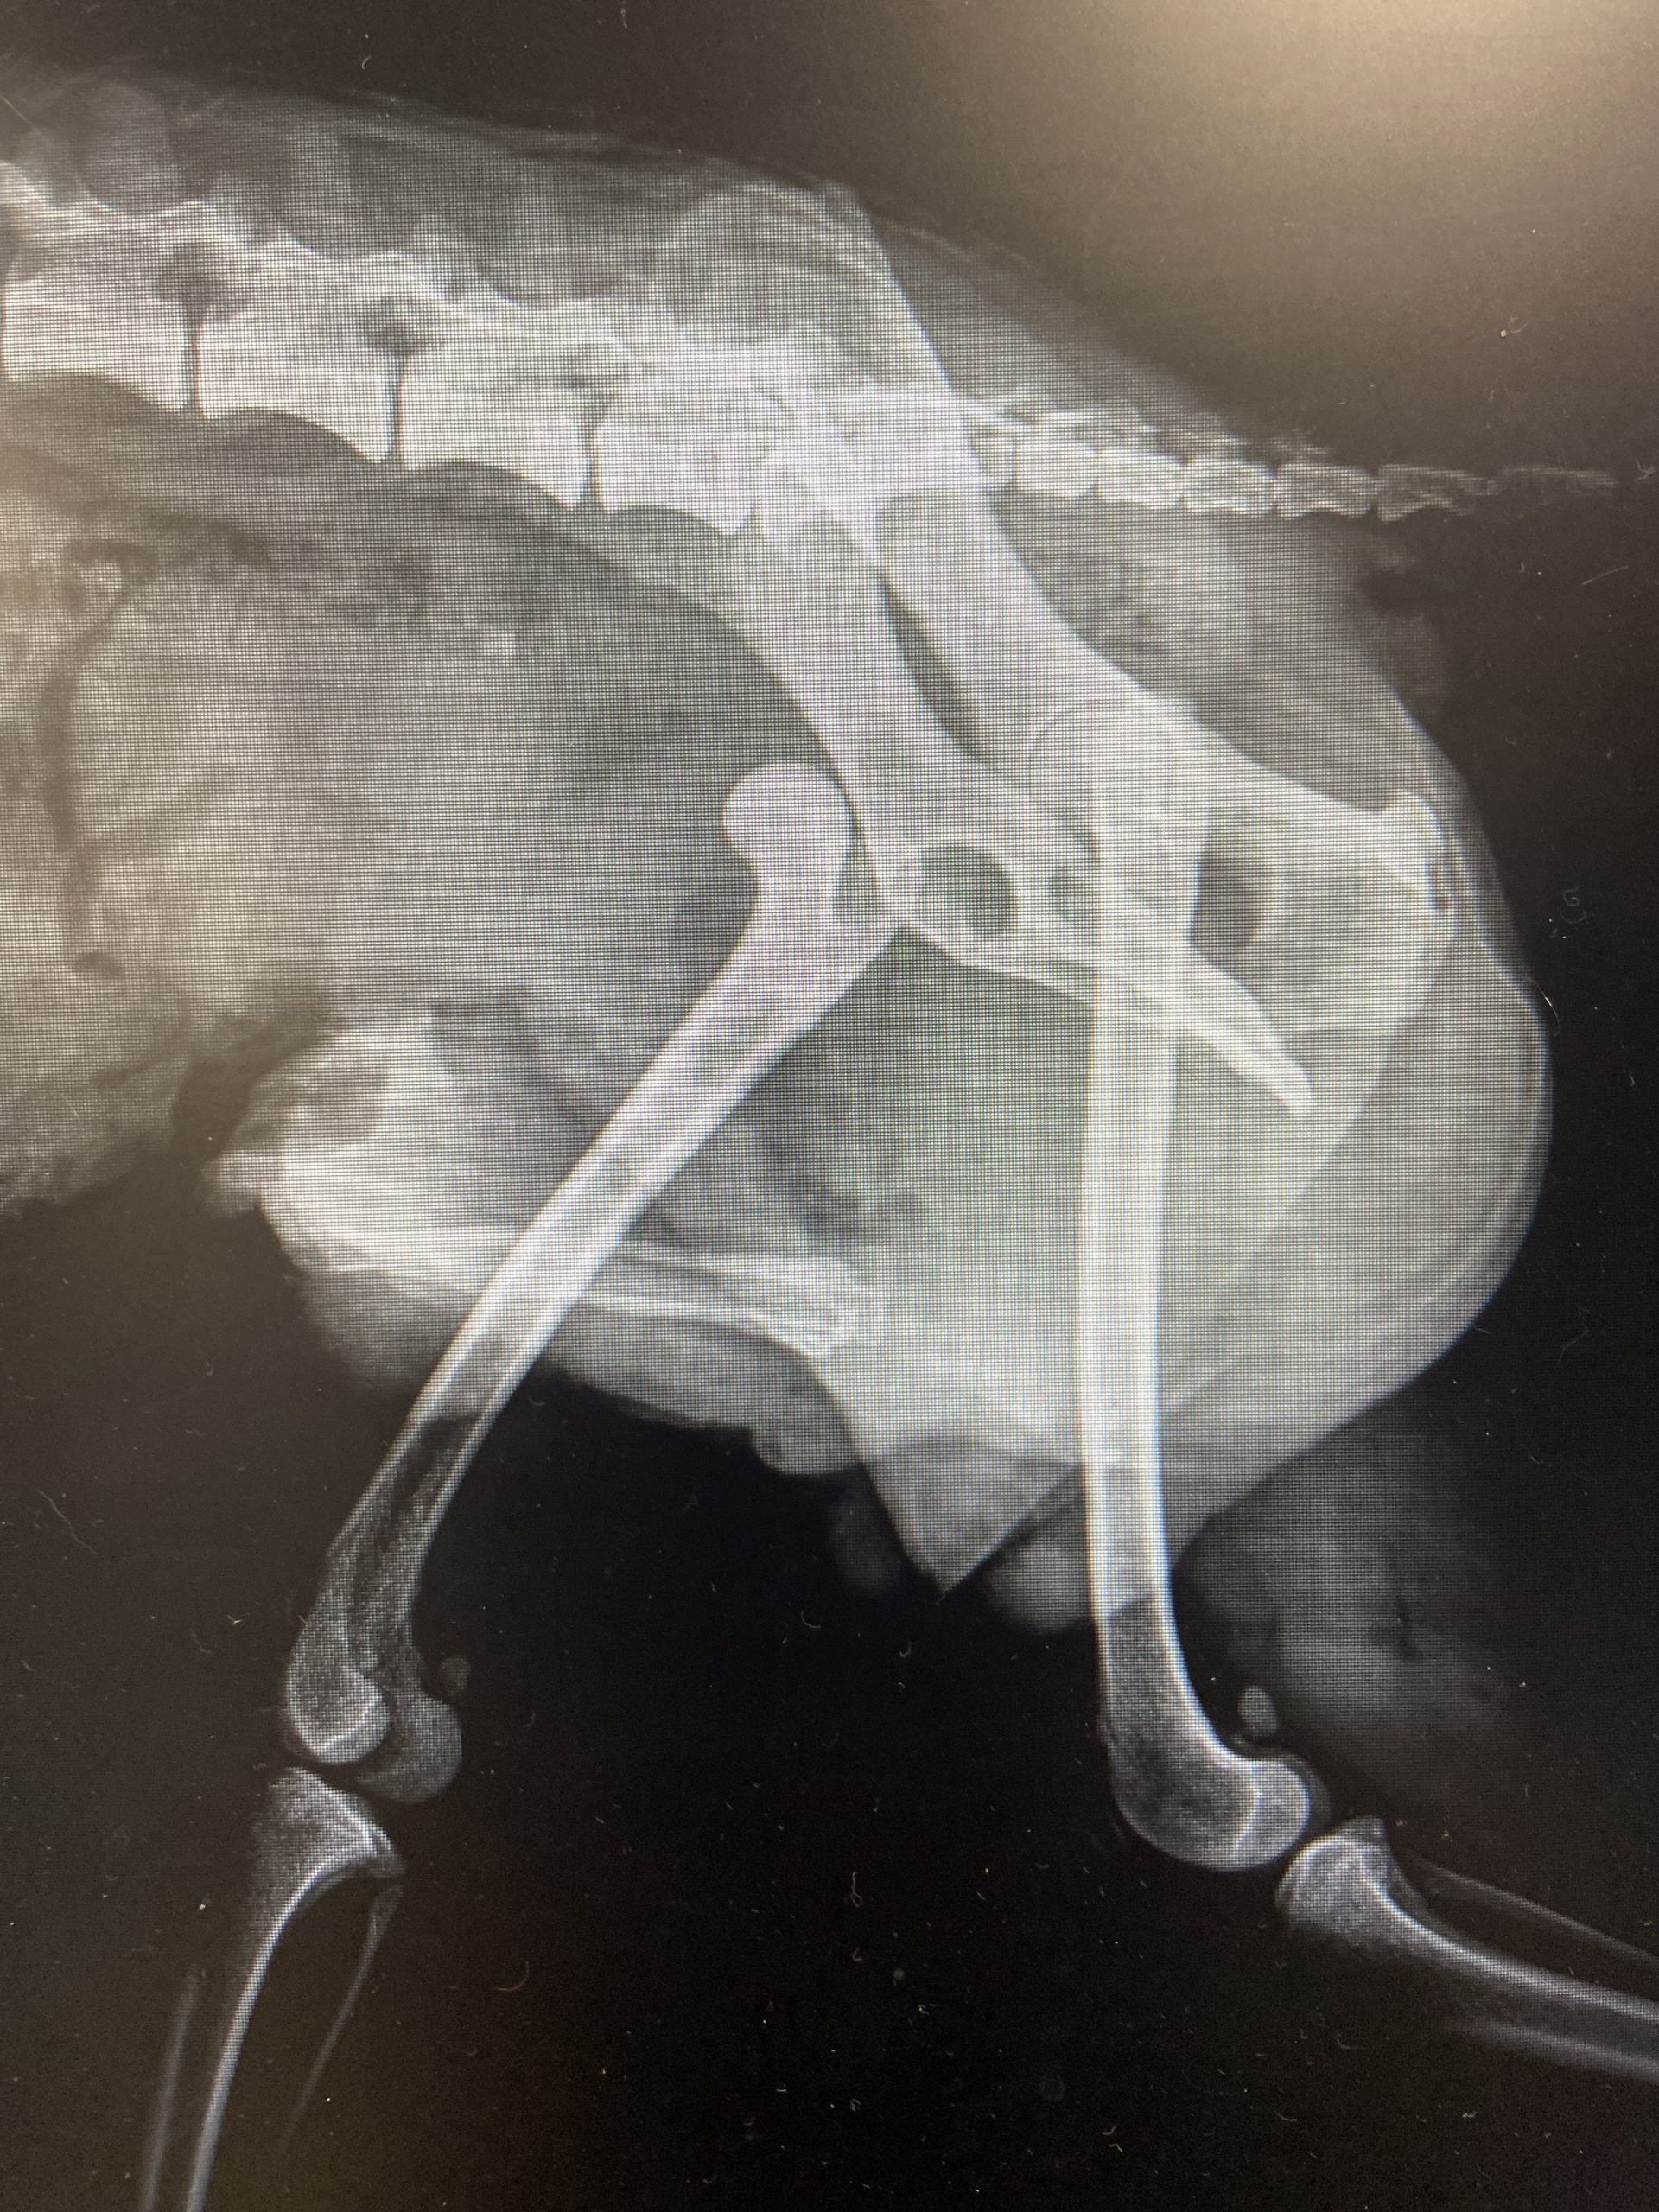

Draco may be just 7 pounds, but his spirit is larger than life! This adorable Pomeranian is a true testament to resilience, joy, and the power of love. After overcoming a serious injury, Draco has healed beautifully and is now thriving, happy, confident, and ready to find his forever family.

Thanks to the incredible care of our veterinary team, Draco made a full recovery and hasn’t let his past slow him down one bit. Today, he’s a cheerful, fluffy little guy who loves life and embraces each day with enthusiasm.